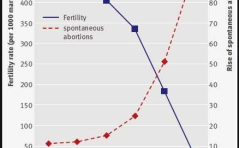

Fortpflanzungsmedizin aktuell - Lifestyle und Kinderwunsch

Kinderwunschpaare fragen oft, was sie selbst zur Verbesserung ihrer Fruchtbarkeit beitragen können. Dies ist ein Grund, weshalb das Thema „Lifestyle und Kinderwunsch“ bei den meisten Paaren auf grosses Interesse stösst. Was sind „Lifestyle“-Faktoren im ... PDF Dokument